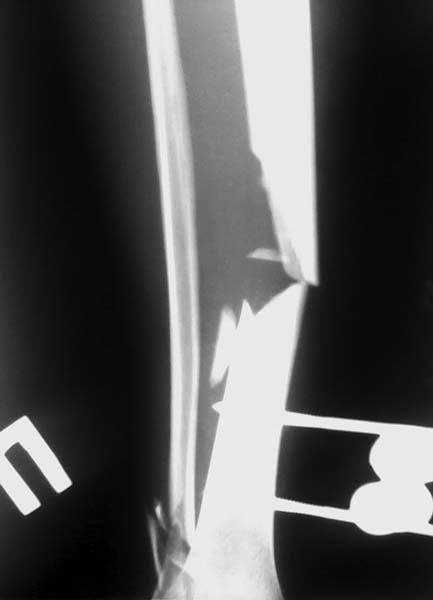

Re: открытый перелом голени - тактика лечения?

АВФ наложили мы при поступлении стабилизационный. Сейчас аппарат сняли, наложили гипсовую повязку чтобы зажили раны в области проведения стержней. Исходная рана (в результате травмы) заживает первично, никаких проблем с ней нет. Склоняемся к БИОСу, вопрос один-откуда взять лучше трансплантат (из малоберцовой кости рядом или на другой ноге), когда лучше прооперировать- чтобы не осложнилось инфекцией. Спасибо ответившим.